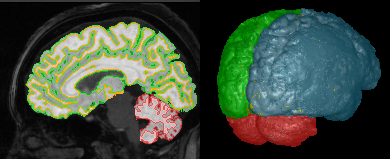

| (a) | (b) | (c) |

Second, given that the 3D extension of ISF simply requires a different choice of adjacency relation, we present a comparison between the best ISF method for this application (ISF-GRID-MEAN with ), the only baseline with 3D implementation (SLIC), and the hybrid approach (SLIC-ISF) on volumetric MR images of the brain. In this dataset, there are three objects of interest: cerebellum, left and right brain hemispheres (Figure 8a). Segmentation creates supervoxels as shown in Figure 8b. Supervoxels with more than 50% of their voxels inside a particular object are labeled as belonging to that object, otherwise they are considered as part of the background or other objects. Effectiveness is measured by f-score for three supervoxel resolutions, given the usual image sizes: low (), medium (), and high (). Table I shows the results of this experiment, using a 64 bit, Core(TM) i7-3770K Intel(R) PC with CPU speed of 3.50GHz. It is not a surprise that ISF outperforms SLIC in effectiveness. However, SLIC is exploiting parallel computing 444Without parallel computing, SLIC would take from 19s-23s of processing time for to supervoxels. and given that SLIC-ISF is twice faster than ISF, their equivalence in performance above medium superpixel resolution is an excellent result. Another interesting observation is that ISF performs better for a value of () lower than (i.e., more regular supervoxels).

Figures 8c-d show another example using ISF-GRID-MEAN, where the specification of 10 supervoxels using segments the patella bone as one of the supervoxels.